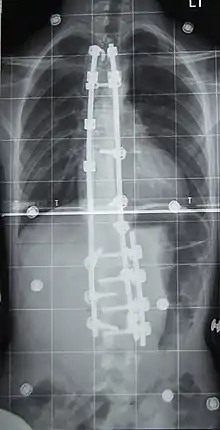

Surgery

Surgery is usually recommended by orthopedists for curves with a high likelihood of progression (i.e., greater than 45–50° of magnitude), curves that would be cosmetically unacceptable as an adult, curves in people with spina bifida and cerebral palsy that interfere with sitting and care, and curves that affect physiological functions such as breathing.[101][102]

Surgery is indicated by the Society on Scoliosis Orthopaedic and Rehabilitation Treatment (SOSORT) at 45–50°[4] and by the Scoliosis Research Society (SRS) at a Cobb angle of 45°.[103] SOSORT uses the 45–50° threshold as a result of the well-documented, plus or minus 5° measurement error that can occur while measuring Cobb angles.[103]

Surgeons who are specialized in spine surgery perform surgery for scoliosis. To completely straighten a scoliotic spine is usually impossible, but for the most part, significant corrections are achieved.[104]

The two main types of surgery are:[105]

- Anterior fusion: This surgical approach is through an incision at the side of the chest wall.

- Posterior fusion: This surgical approach is through an incision on the back and involves the use of metal instrumentation to correct the curve.